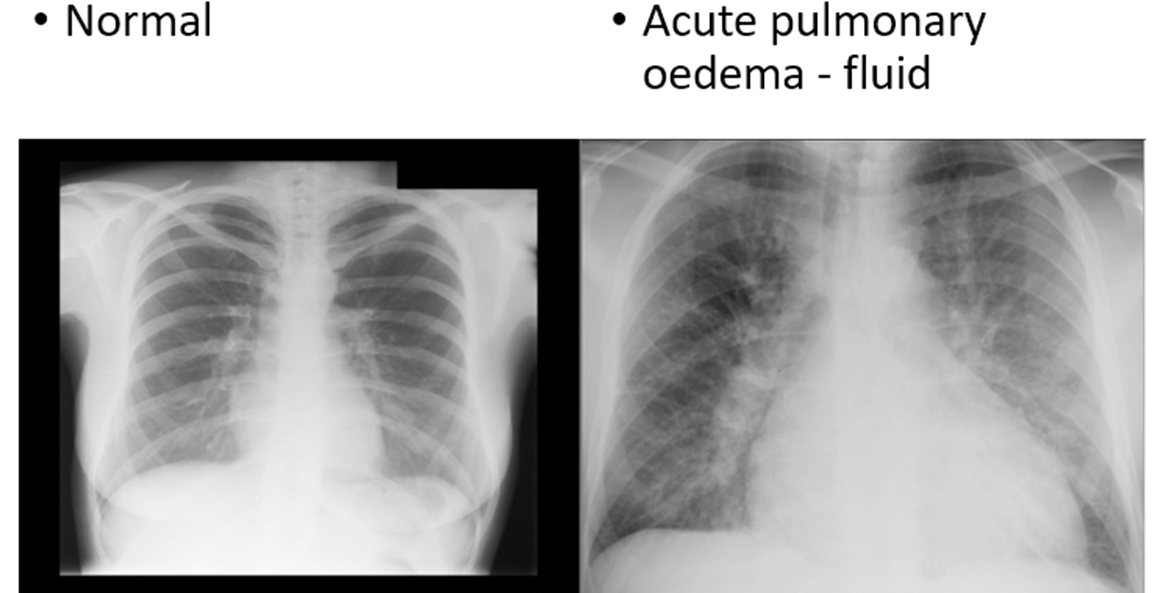

what pathology occurs when the kidney start dysfunctioning?

•Acute pulmonary oedema - fluid

(salt and water imbalance)